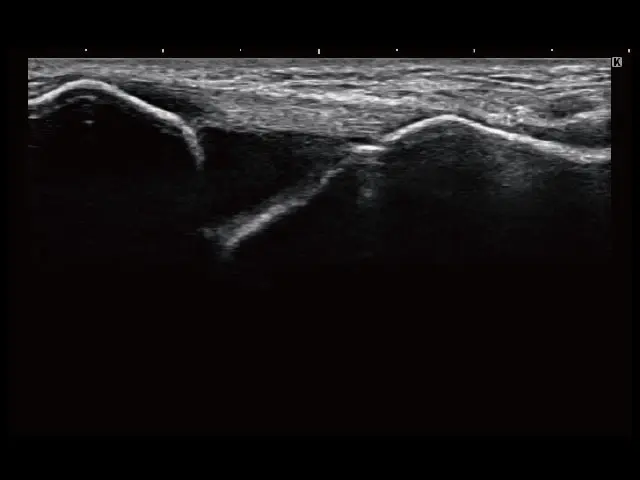

イメージギャラリー

イメージ画像を表示する